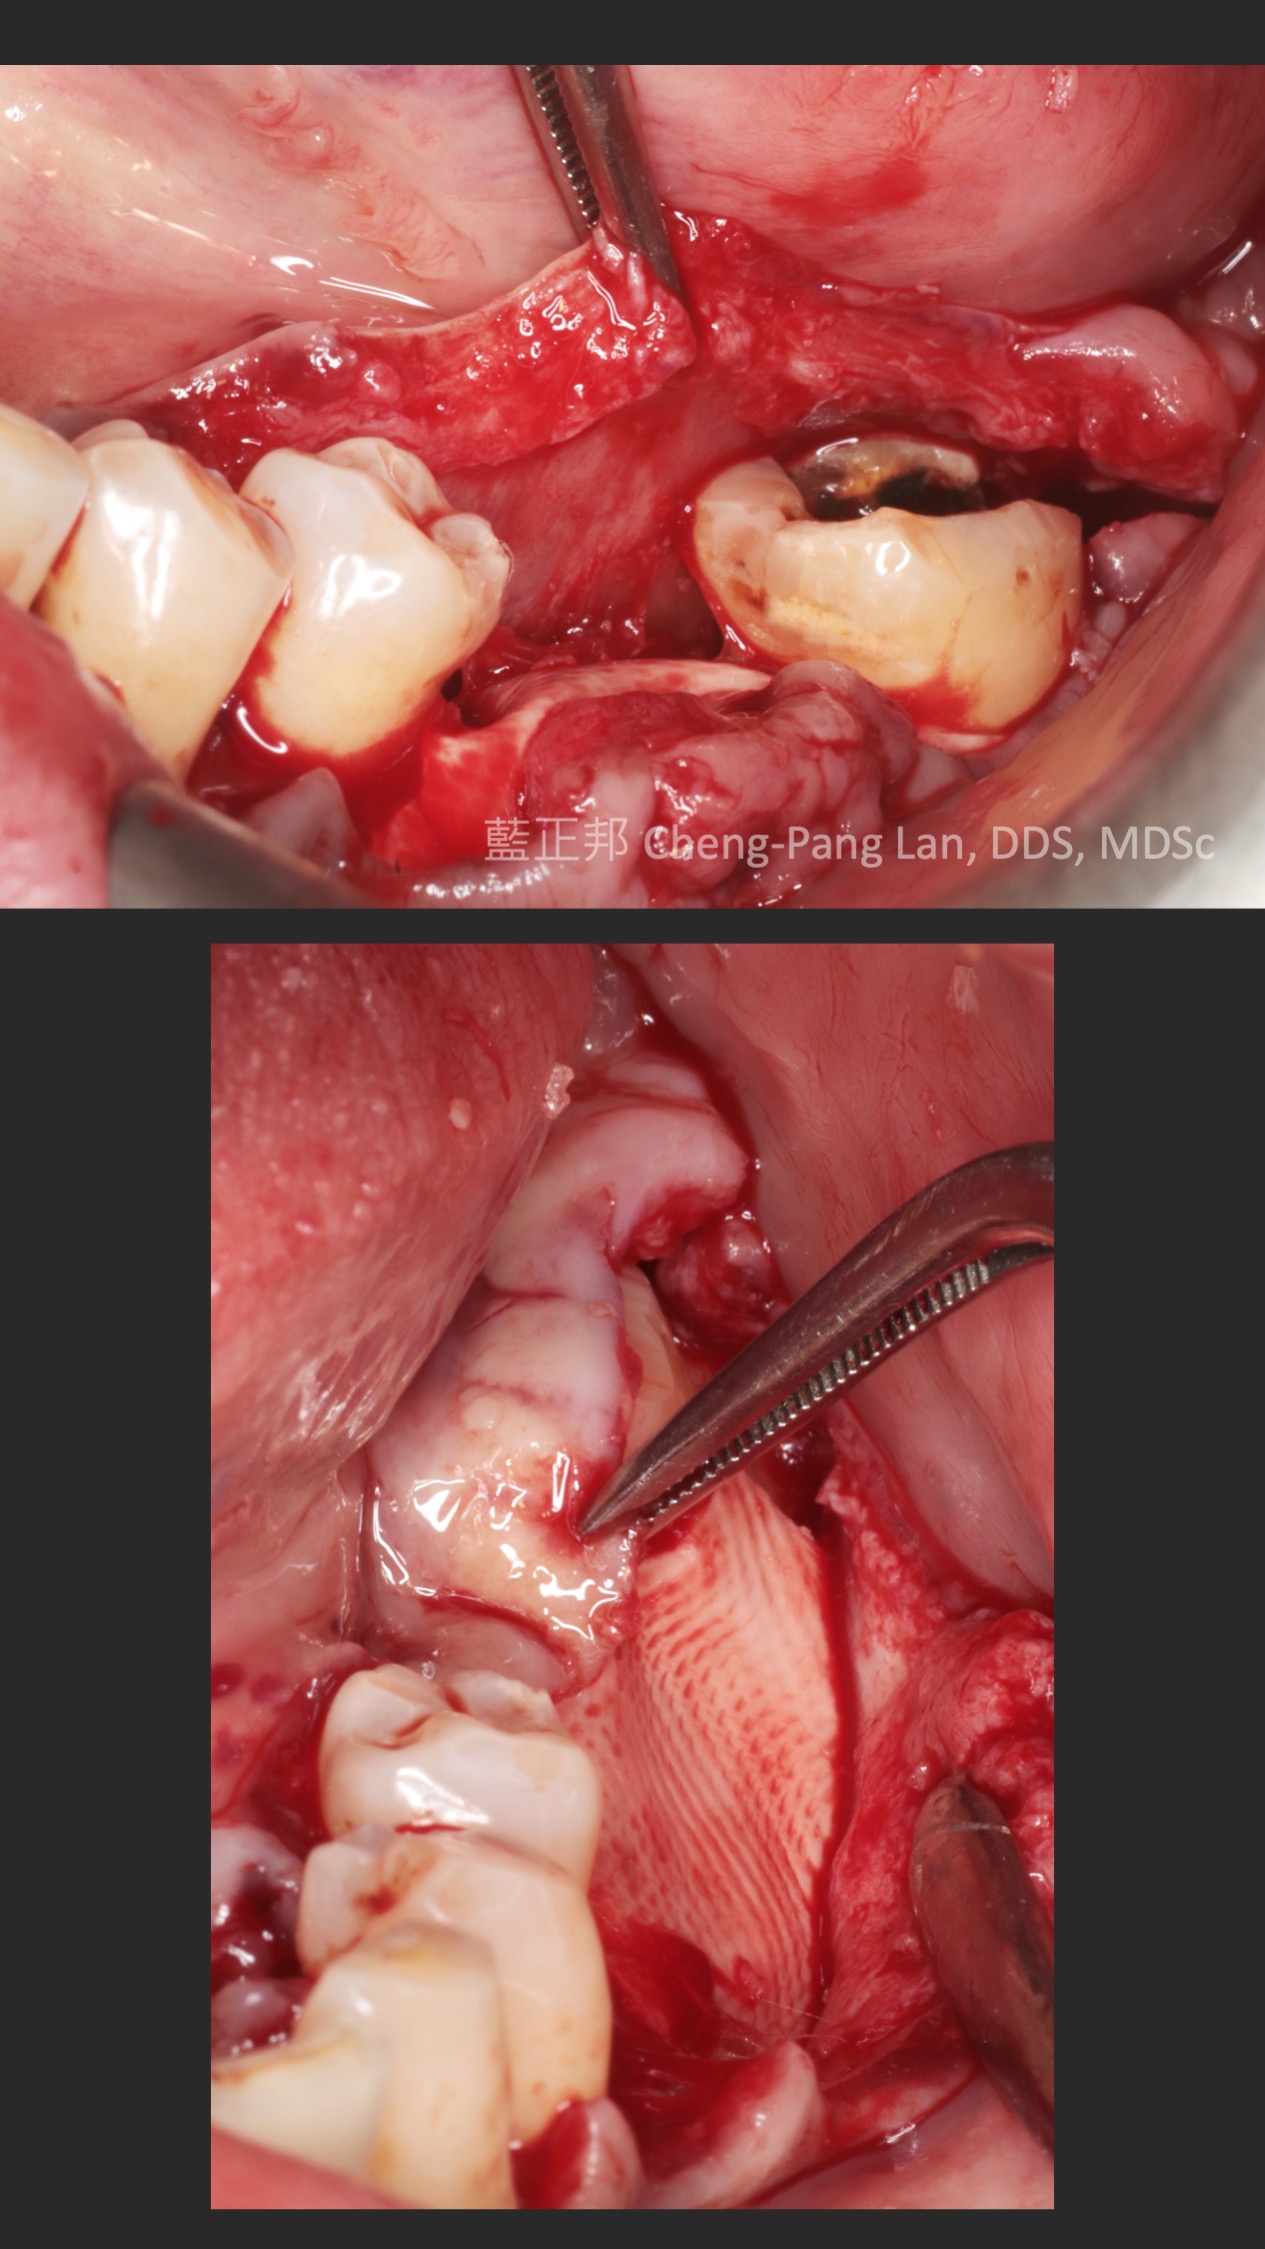

12 Years of Lateral-window Sinus Lift

2010年,台大第二年剛開始。這是我第一台鼻竇開窗手術,還記得很快地用骨刀切割,順利進入鼻竇。

但是翻到後面,遇到困難,只翻一半就遇到瓶頸,由台大老師接手翻完,之後回到我再放入材料並縫合。

這十二年來,口內狀態,加上X光檢查,一直都算穩定。但是回顧起來,病患其實血糖不低,加上抽菸,危險因子算多了。

回顧還發現,其實第一次做開窗就用手繪圖了,有興趣如何準備開窗手術的初學者,我寫了一篇在這裡